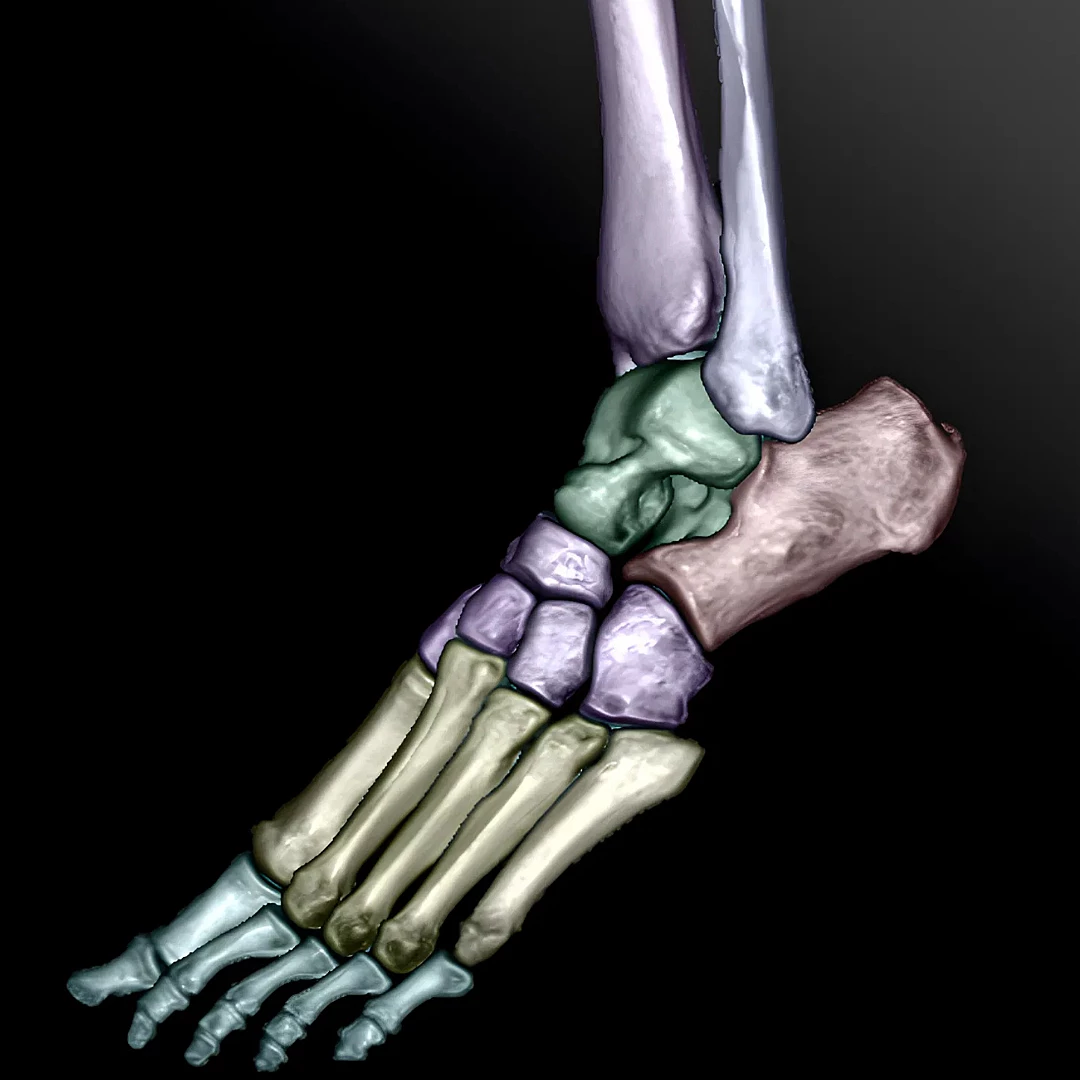

Advanced Bone and Joints CT provides detailed images of bones and joints to evaluate fractures, arthritis, and complex skeletal conditions. It’s ideal for orthopedic diagnosis, surgical planning, and sports injury assessment.